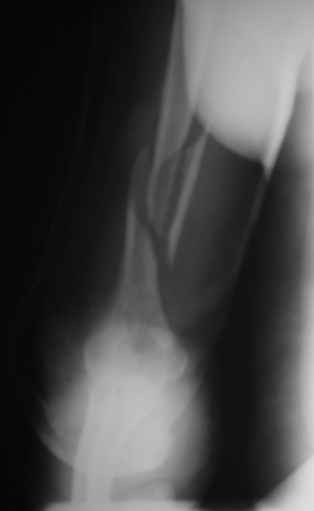

Огромное спасибо всем принимающим участие в дискуссии. Вначале отвечу на поступавшие персональные вопросы: 1. обстоятельства травмы - соревнования по армрестлингу (от себя замечу, что у военных нередкая травма в последнее время! На мой взгляд это связано с вовлечением в это дело неподготовленных людей - командирам нравится, т.к. в плане реквизита намного легче организовать чем традиционное перетягивание каната...). 2. в отношении провокационной составляющей - она присутствует, но лишь в той степени в какой любое инициирование дискуссии несет в себе элемент провокации... 3. про актуальность консервативного лечения - мне кажется это актуально всегда и при любой локализации если врач владеет методом, например, часто наблюдал великолепные функциональные результаты консервативного лечения переломо-вывихов голеностопных суставов... Тут только надо помнить, что "консервативное" это тоже лечение (контроль, тяги, перекладывание повязок), а не просто накладываем гипс и через энное время говорим, что не получилось и берем на операцию.

Теперь непосредственно по больному. Лечим функциональной повязкой, добились вот чего (приложение). Будем признательны за дальнейший комментарий - мое мнение, что можно продолжить без операции.